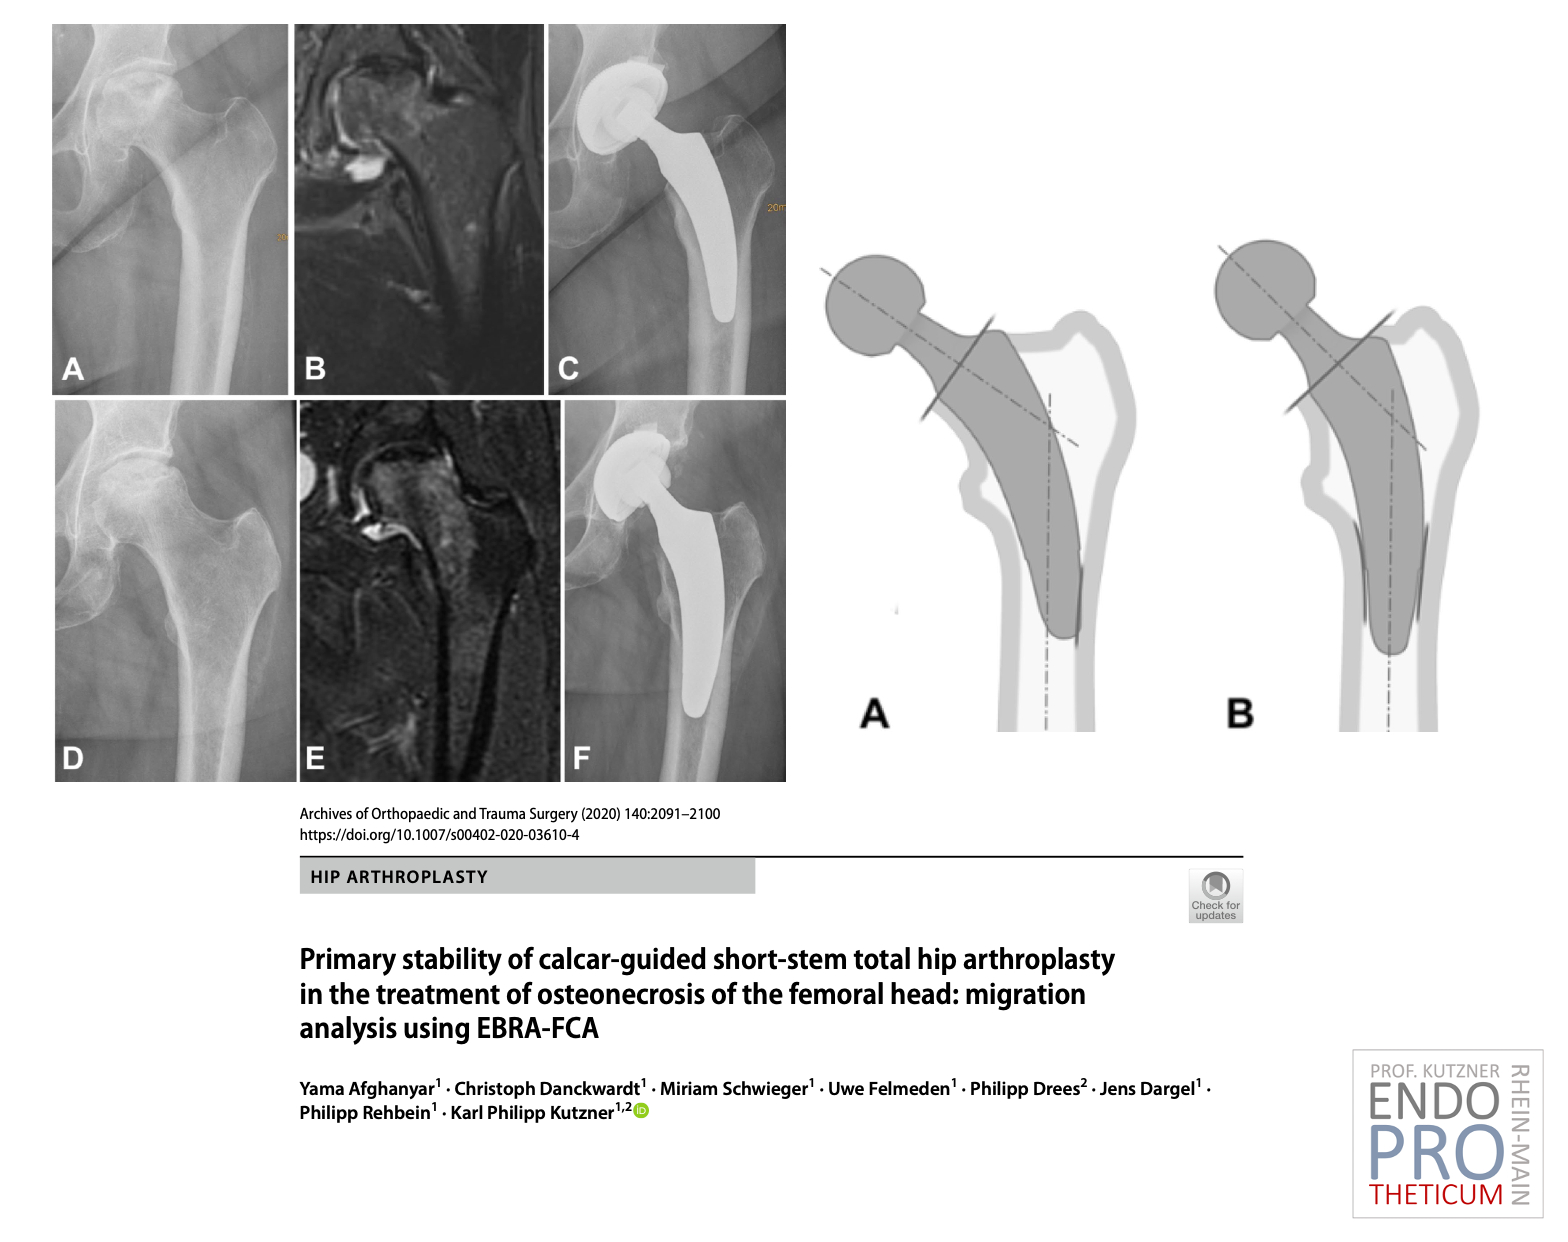

Концепция современных коротких ножек с калькарным наведением при эндопротезировании тазобедренного сустава направлена на точную реконструкцию индивидуальной анатомической геометрии бедра.

щадящая для костей и мягких тканей техника имплантации в сочетании с физиологической нагрузкой на часть бедренной кости вблизи сустава, чтобы сохранить кость в долгосрочной перспективе.